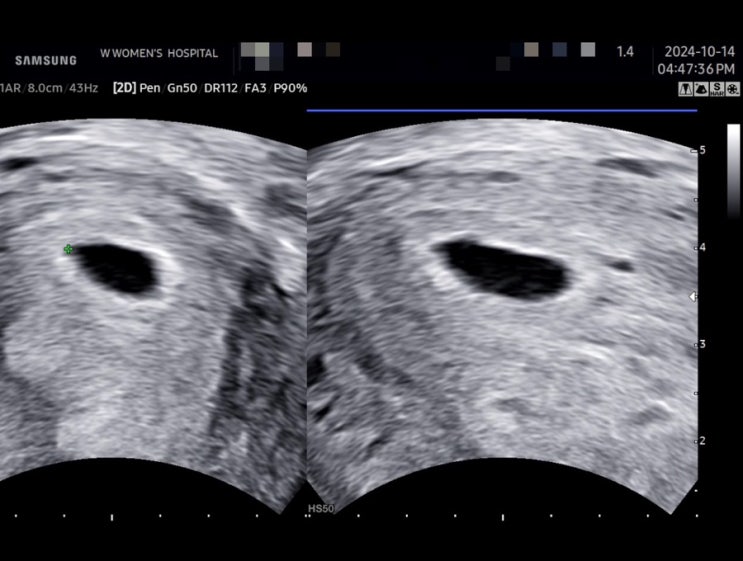

[임신기록] 10주, 11주, 12주 입덧헬 체력헬

임신 12주 차입니다. 여전히 입덧은 그대로입니다. 워킹맘 연말은 상당히 바쁩니다! 그래도 첫째 딸도 뱃속...